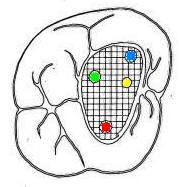

Cuarto conducto en molares superiores (Color amarillo conducto mesio-palatino) |

Estos conductos pueden unirse a distintos niveles, terminando en un foramen único o ser de trayectoria independiente hasta el ápice y terminar en forámenes separados. Son atrésicos y de difícil tratamiento en especial el palatino. La raíz distovestibular tiene dimensiones menores que la mesiovestibular y no presenta curvaturas acentuadas. El conducto distovestibular (Color verde) por lo general es atrésico y puede presentar curvaturas. La raíz palatina es la más voluminosa de forma cónica y sección circular. Puede ser recta o curva. Cuando es curva, el sentido e la curva es hacia vestibular. El conducto palatino (Color rojo) es amplio y de fácil acceso, rectilíneo o con una curva leve hacia vestibular. |